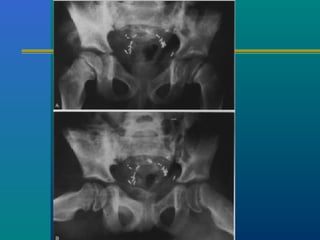

TB HIPTB HIP

Not so uncommon in our

practice

Limp – commonest presentation

Night cries

Stiffness

Wasting

Fever

Weight loss

TB HIP- X-RAYTB HIP- X-RAY

 Osteoporosis

 Travelling acetabulum

 Dislocated hip

 Mortar and pestle appearance

 Perthes type

 Protrusio acetabuli

 Destruction of head

 ATT

 Traction

 Splintage

 Surgery – last resort